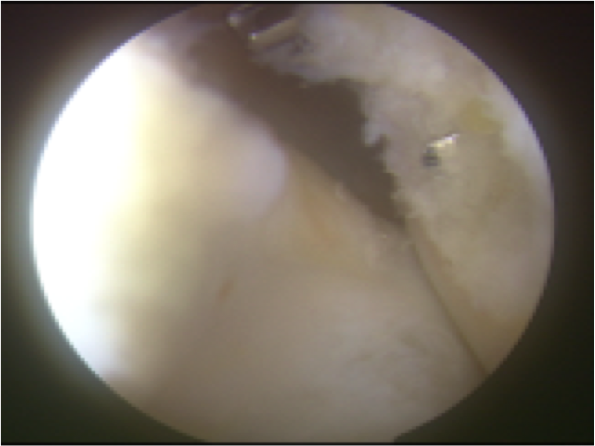

ACL再建

大腿骨孔作成グラフト挿入再建靭帯